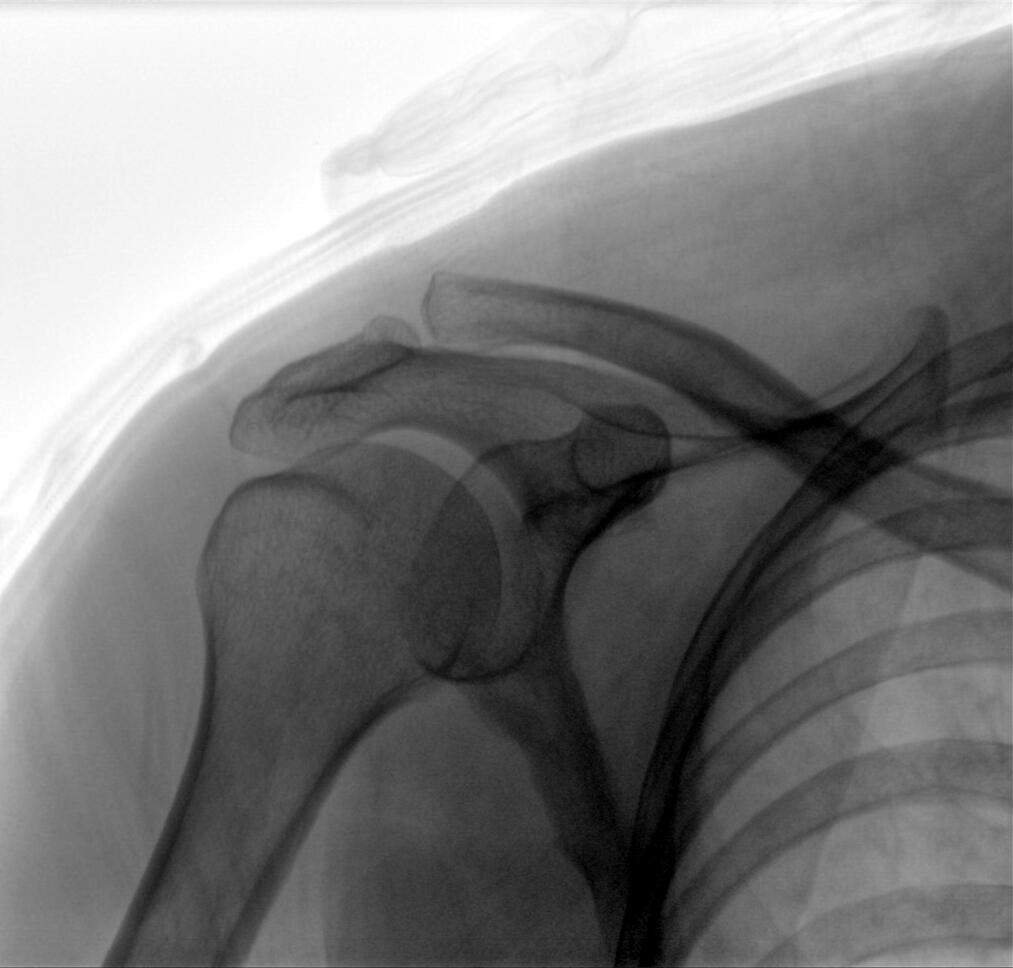

PLX118WF-Plus配備了兩種平板尺寸,大尺寸動(dòng)態(tài)平板探測器成像面積較傳統平板探測器提升了25%以上,在視野需求大的手術(shù)中,便于醫生更好定位病灶點(diǎn),規劃手術(shù)方案,減少因視野范圍不足而多次透視、點(diǎn)片造成的不便,不僅提高了手術(shù)效率,也減少了輻射劑量。